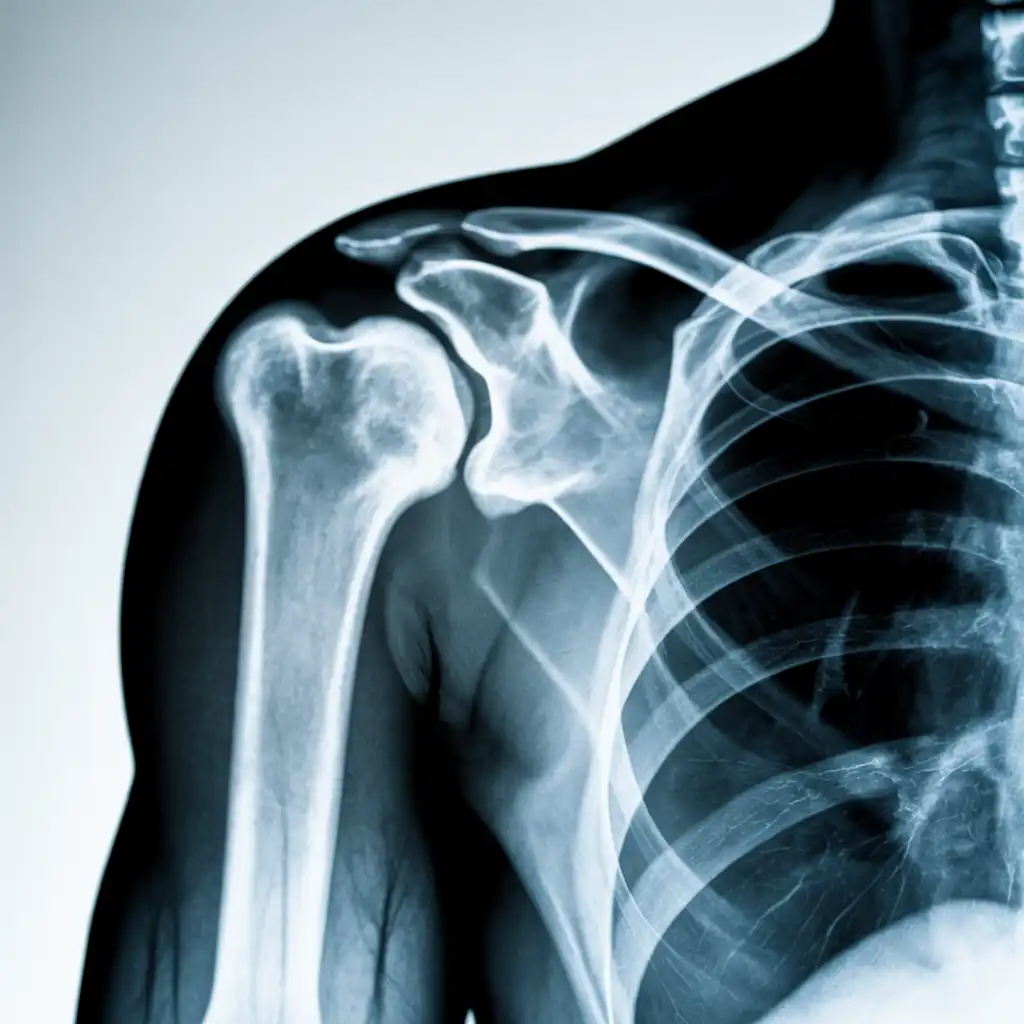

Da anni offriamo un servizio di radiografie a domicilio pensato per garantire ai nostri pazienti la stessa qualità diagnostica degli esami eseguiti in ospedale, ma con la comodità e la sicurezza della propria casa.

Abbiamo effettuato migliaia di esami direttamente presso abitazioni, residenze e strutture assistenziali, utilizzando apparecchiature digitali portatili certificate e procedure rapide e sicure.